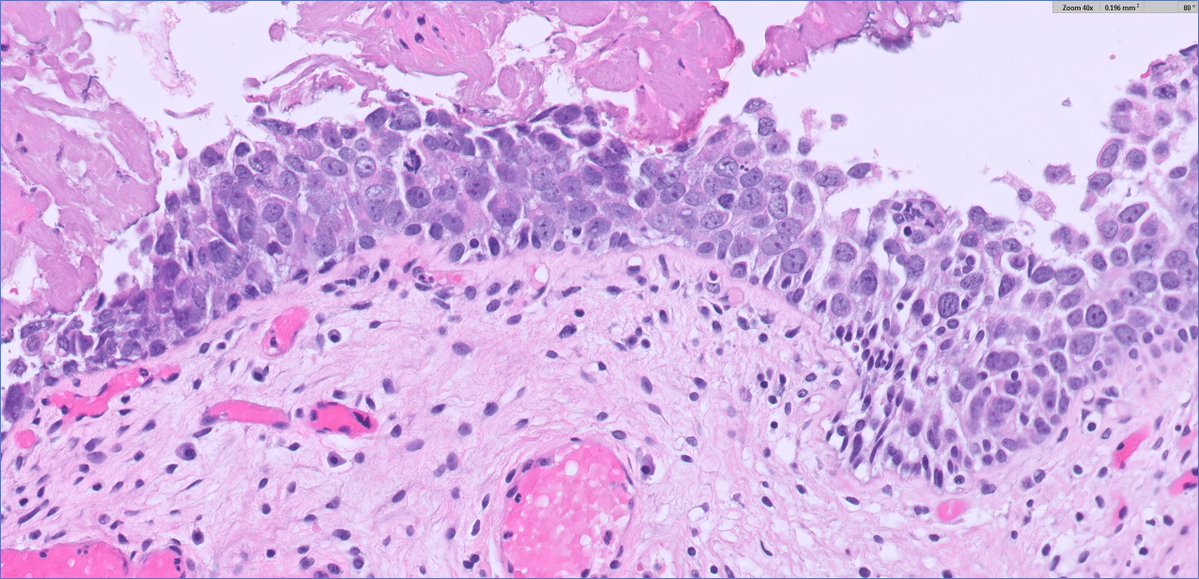

Classic histology snapshot: bladder mucosa packed with inflammatory cells surrounding characteristic schistosome eggs. A striking reminder of how parasitic infections like schistosomiasis can drive chronic inflammation and long-term complications in the urinary tract. #GUpath